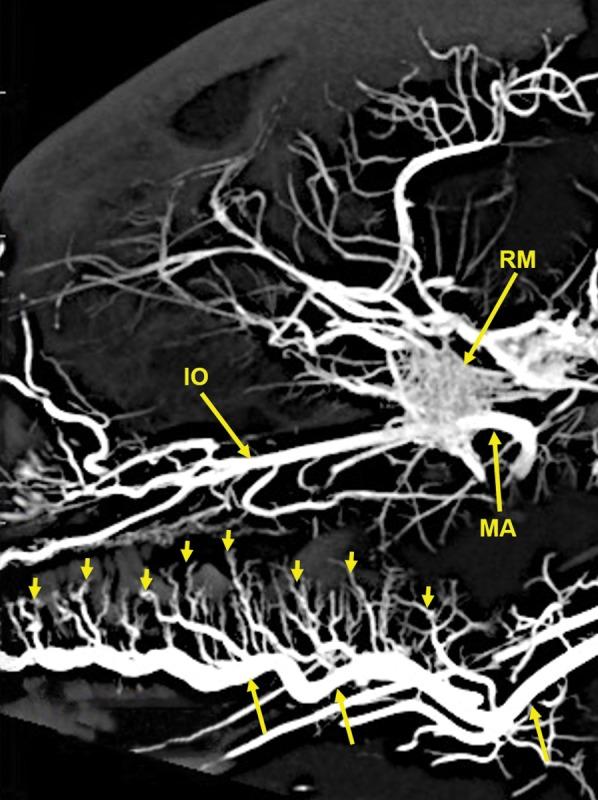

The objective of this study was to investigate the possibility of obtaining high-resolution multiplanar computed tomography (CT) imaging of the cranial arterial circulation of the cat (Felis catus), the rete mirabile, and components of the skull, utilizing preserved cat specimens with an arterial system that was injected with a radiopaque contrast compound in the early 1970s. Review of the literature shows no high-resolution CT studies of the cat's cranial circulation, with only few plain radiographic studies, all with limited cranial vascular visualization. In view of the inability of the radiographic techniques available from 1970s to mid-2000s to provide high-resolution imaging of the arterial circulation within the intact skull and brain of the cat, without dissection and histologic sectioning and disruption of tissues, no further imaging was performed for many years. In 2010, a high-resolution micro CT scanner became available, large enough to scan the entire nondissected head of the arterially injected cats. All the obtained CT images were processed with a software program that provided 3D volume rendering and multiplanar reconstruction with the ability to change the plane angulation and slab thickness. These technical features permitted more precise identification of specific arterial and bony anatomy. The obtained images demonstrated, with a nondestructive method, high-resolution vascular anatomy of the cerebral, orbital, facial arterial system, the rete mirabile, and skull bone components of the cat, with details not previously described in the literature. Anat Rec, 302:1958-1967, 2019. © 2019 The Authors. The Anatomical Record published by Wiley Periodicals, Inc. on behalf of American Association of Anatomists.

本研究旨在探讨利用上世纪 70 年代早期向动脉系统内注入造影剂的保存猫标本,获取猫颅动脉循环、网状血管和颅骨成分的高分辨率多平面计算机断层扫描(CT)成像的可能性。文献回顾表明,目前尚无关于猫颅循环的高分辨率 CT 研究,仅有少数平片研究,但都仅能有限地显示颅血管。鉴于上世纪 70 年代至 2000 年代中期的放射技术无法在不进行解剖和组织学切片及破坏的情况下,提供猫完整颅骨和大脑内动脉循环的高分辨率成像,因此多年来没有进一步进行影像学检查。2010 年,一种高分辨率的微 CT 扫描仪问世,其体积足够大,可以扫描整个经动脉注射的猫的未解剖头部。所有获得的 CT 图像都使用软件进行处理,该软件具有 3D 容积渲染和多平面重建功能,能够改变平面角度和切片厚度。这些技术特征使特定动脉和骨骼解剖结构的识别更加精确。所获得的图像以非破坏性方法显示了猫的大脑、眼部、面部动脉系统、网状血管和颅骨骨成分的高分辨率血管解剖结构,提供了文献中以前未描述过的细节。解剖学记录,302:1958-1967, 2019. © 2019 作者。解剖记录由 Wiley 期刊出版公司代表美国解剖学家协会出版。